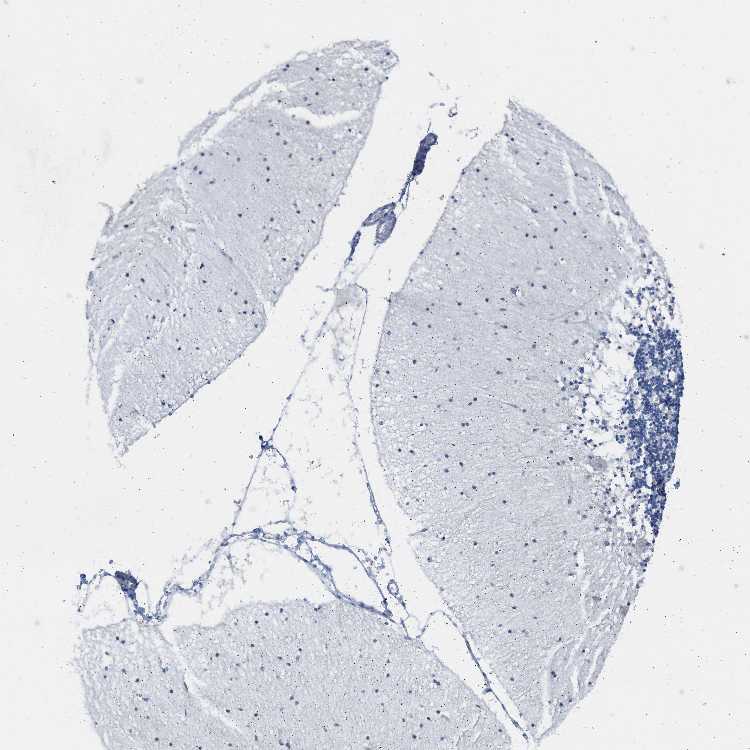

CEREBELLUM - Antibody stainingi

Antibody staining in the annotated cell types in the current human tissue is reported as not detected, low, medium, or high, based on conventional immunohistochemistry profiling in selected tissues. This score is based on the combination of the staining intensity and fraction of stained cells.

Each image is clickable and will lead to virtual microscopy that enables deeper exploration of all samples and also displays staining intensity scores, fraction scores and subcellular localization as well as patient and tissue information for each sample.

Antibody HPA001383Antibody CAB000043Antibody CAB020416Antibody CAB062555

Purkinje cells MediumNot detectedNot detectedNot detected

Cells in granular layer Not detectedNot detectedNot detectedNot detected

Cells in molecular layer LowNot detectedNot detectedNot detected